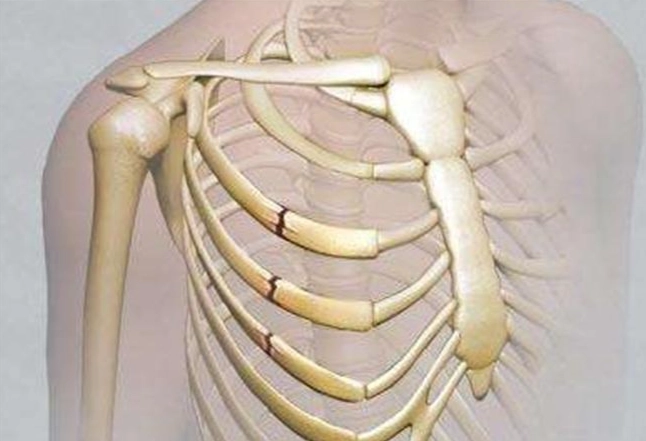

肋骨骨折後,身體會啟動自然的愈合過程,包括炎症期、修復期和重塑期。這段期間,營養攝取直接影響骨骼的再生能力。如果吃了不該吃的東西,可能會干擾這些階段,導致恢復延遲或併發症。例如,高鹽分食物會引起水腫,增加胸腔壓力,讓呼吸都變得更痛苦。而辛辣食物則可能刺激神經,加劇疼痛感。

有些研究指出,飲食控制能減少併發症風險,比如肺炎或感染。肋骨骨折常伴隨呼吸困難,如果飲食不當導致腹脹或炎症,可能會讓呼吸更吃力。這點我深有體會,當初因為貪吃鹹酥雞,結果水腫搞得我連深呼吸都痛,真是自作自受。